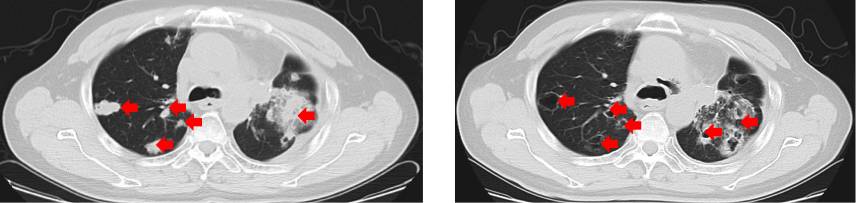

(患者服用阿帕替尼后肺部病灶形成空洞)

38例三线及三线后口服阿帕替尼的原发性肺癌患者中,37例口服剂量为250mg,1例患者服用500mg作为起始剂量。治疗期间,有20例患者(占比52.6%)形成了肺部空洞。空洞的形成在年龄、性别、肺癌分型、分期、手术史及阿帕替尼特征反应等分层因素上均未显示显著差异。空洞形成伴随短期CEA升高,形成空洞病灶和未形成空洞病灶的患者中,发生CEA升高的百分比分别是65.0% 和 5.6%。形成空洞病灶的患者中位PFS为11.25个月(95% CI, 10.16-13.64),相较未形成空洞病灶的患者中位PFS(6.11个月,[95% CI, 6.01-6.71];P<0.0001)有明显的提高。此外,发生短期CEA升高的患者中位PFS相较未发生短期CEA升高的患者中位PFS也有提高,但未做出明显统计学差异(10.64个月 [95% CI, 10.09-14.14] vs. 6.14个月 [95% CI, 6.07-8.13];P=0.0703)。

64例口服阿帕替尼的实体瘤伴随肺转移癌患者中,23例胃癌患者(占比35.9%)、14例结直肠癌患者(占比21.9%)、10例肝癌患者(占比15.6%)。有98.3%的患者口服剂量为250mg,其余患者服用500mg作为起始剂量。治疗期间,也有20例患者(占比31.3%)形成了肺部空洞。由于这些患者在治疗前的影像检查中,均未见空洞病灶,因此认为肺部空洞的形成是患者服用阿帕替尼导致的。空洞的形成在年龄、性别、肺癌分型、分期、手术史及阿帕替尼特征反应等分层因素上均未显示显著差异。形成空洞病灶和未形成空洞病灶的患者中,发生短期CEA升高的百分比分别是85.0% 和 34.1%。形成空洞病灶的患者中位PFS为15.44个月(95% CI, 12.12-20.65),相较未形成空洞病灶的患者中位PFS(6.71个月,[95% CI, 6.11-8.13];P<0.0001)有明显的提高。此外,发生短期CEA升高的患者中位PFS相较未发生短期CEA升高的患者中位PFS也有提高,但未显示明显统计学差异(11.15个月 [95% CI, 6.71-15.44] vs. 8.13个月 [95% CI, 6.31-15.57];P=0.3047)。

这两项研究的结果显示阿帕替尼无论是在原发性肺癌还是在实体瘤伴肺转移的患者中,都可能具有诱导肺部空洞产生的趋势,肺部空洞的产生可能伴随CEA的短暂升高,而肺部空洞化有可能对改善患者PFS起到相当积极的影响,对其机制的进一步研究有可能协助发掘潜在的生物标志物,从而对患者的生存及预后发挥积极作用。